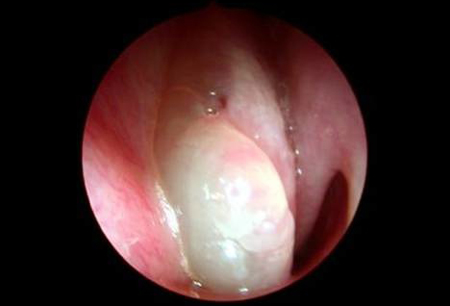

Histologically benign.[Figure caption and citation for the preceding image starts]: Grade 3 nasal polypsFrom the collection of Dr Richard Hewitt [Citation ends].